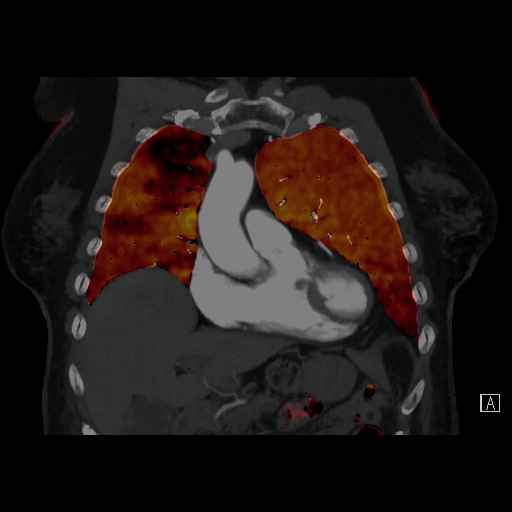

脱水や長時間同じ姿勢を取ることなどで脚の静脈の流れが悪くなり、血栓ができることがあります。その血栓が肺に運ばれて肺動脈を詰まらせてしまうのが肺血栓塞栓症です。CTを用いることで肺動脈内の血栓を造影欠損像として直接描出できます。さらに、デュアルエナジー撮影法を利用すると肺血流の機能情報を可視化することができます。

デュアルエナジーイメージングによる肺灌流評価CT(治療前と抗凝固薬服用後)